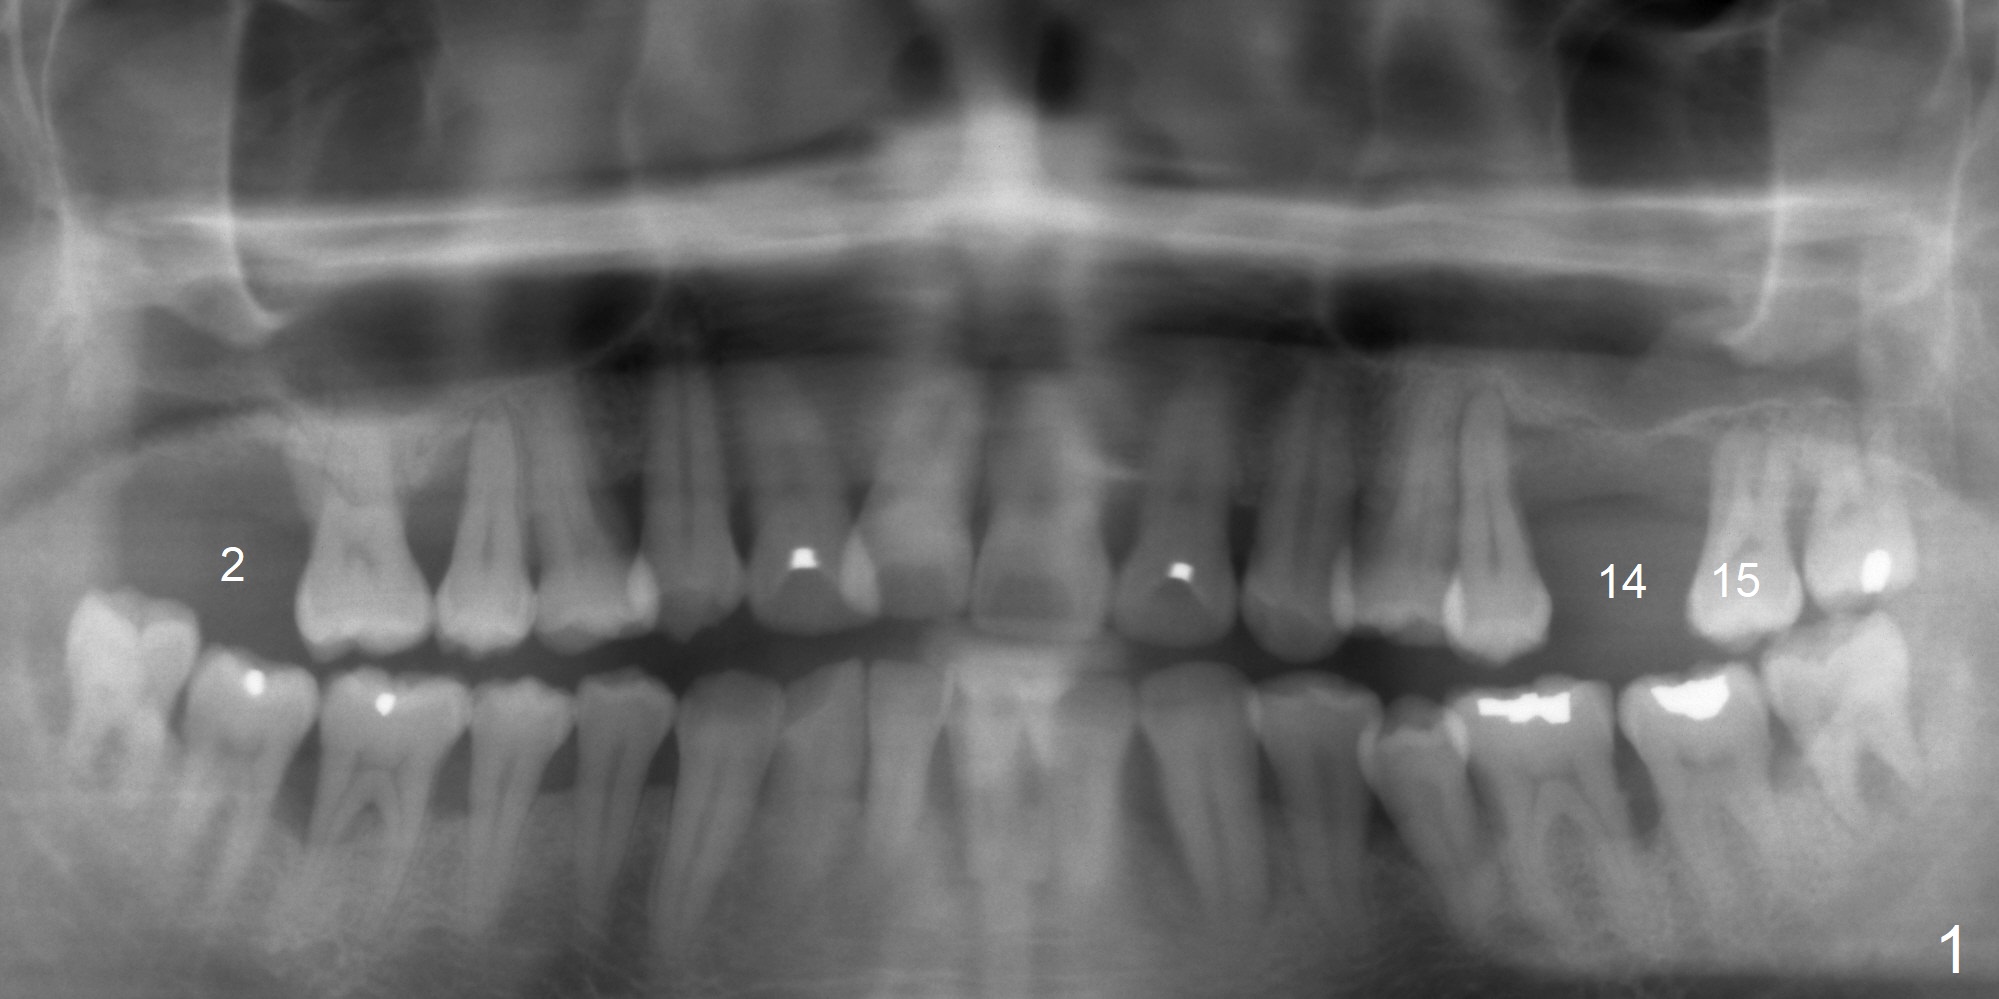

When a 38-year-old man presented to the office 10 years ago, there were 2 missing teeth #2 and 14 with 5.8 mm and 1 mm bone height, respectively (Fig.1). Later the tooth #15 was extracted. A 6x11 mm implant was placed with internal sinus lift at #2 first. Two of 5x11 mm tissue-level implant were placed with lateral window sinus lift at #14,15. The implant at #14 is loose 3 months post cementation and dislodges later. Four months post bone graft, a 5x7 mm IBS implant was placed with CMC technique. With progressive loading at #14, the crown functions 1 year post cementation with the thick bone (Fig.2 *).